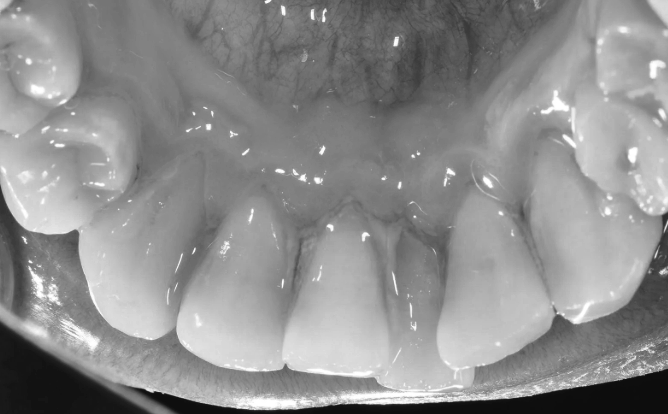

혹시 치아틀어짐 방치하고 계신가요?

'치아가 삐뚤어져서 고민'이신 분이실 겁니다.

많은 분들이 치아 틀어짐을

단순히 '보기 싫은' 문제로만 생각하십니다.

하지만 이는 마치 빙산의 일각만

보는 것과 같습니다.

틀어진 치아는 제대로 된

저작 기능을 수행하지 못합니다.

더욱 심각한 것은 치아 사이사이에

음식물이 끼기 쉬워진다는 점입니다.

칫솔이 닿지 않는 부분에 치태가 쌓이고,

이것이 치석으로 변하면서 잇몸염과

치주질환으로 발전합니다.

결국 건강했던 치아까지 흔들리게 되어

발치를 해야 하는 상황에 이를 수 있습니다.